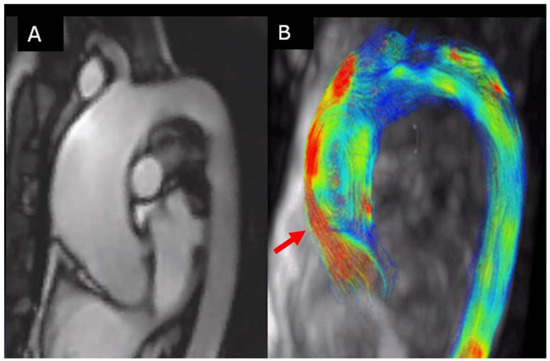

6.2. Aortic Flow Hemodynamic Parameters

- CMR offers the unique opportunity to transition from anatomic to dynamic imaging of the ascending aorta by assessing its functional properties and blood flow patterns. 4D-flow CMR may provide new parameters to predict the rate of progressive aorta enlargement.